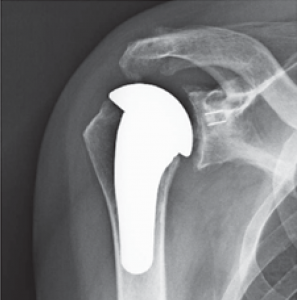

In diesem Fall kann das Gelenk durch ein sog. inverses Prothesen-System nach Prof. Paul Grammont ersetzt werden. Hierbei wird eine „Halbkugel“ (Glenosphäre) auf die ursprüngliche Pfanne aufgeschraubt und eine konvex geformte „Humeruspfanne“ im Oberarmknochen fixiert (Abb. 48). Der Oberarm wird dadurch wieder nach „unten“ verlagert und die Funktion des M. deltoideus wird verbessert (Abb. 49).